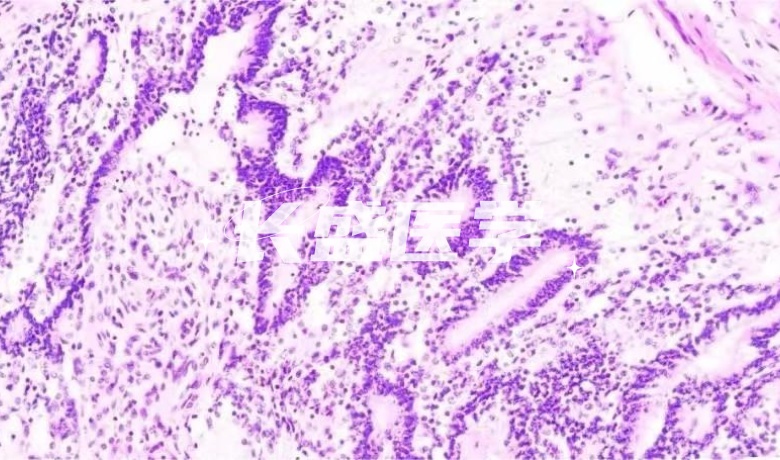

HE staining

HE staining, also known as hematoxylin-eosin double staining, is one of the most basic and commonly used staining methods in the biological field. This method can visualize the nucleus and cytoplasm of cells and tissues, which provides an important help for the observation of pathological morphology.

Hematoxylin-eosin staining, often abbreviated as HE staining, is a widely used staining method. Among them, hematoxylin (hematoxylin) is a cationic dye, the main role is to the nucleus of the basophilic substances stained blue-purple. Eosin, on the other hand, is an anionic dye that stains the cytoplasm and collagen fibers into pink. This staining method is widely used in the biomedical field, and its clear and accurate staining effect provides an important reference for researchers, and is also used in clinical diagnosis and teaching. Because of its high reliability and practicality, HE staining has become one of the important methods in modern biological staining technology.